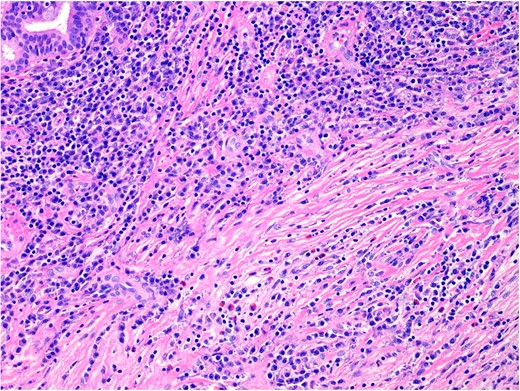

Histopathology demonstrated stromal storiform and perivascular concentric fibrosis with a prominent chronic inflammatory infiltrate (Fig. 2). This consisted of mature lymphocytes, mature plasma cells and eosinophils (Fig. 3). Arteritis (a feature of GPA) was not seen. On digital microscopy, the IgG4 plasma cell counts were 98–120/HPF and IgG4:IgG ratios of 0.4–0.7.

The inflammatory infiltrate is composed of mature lymphocytes, plasma cells and eosinophils. 200× magnification. H&E.